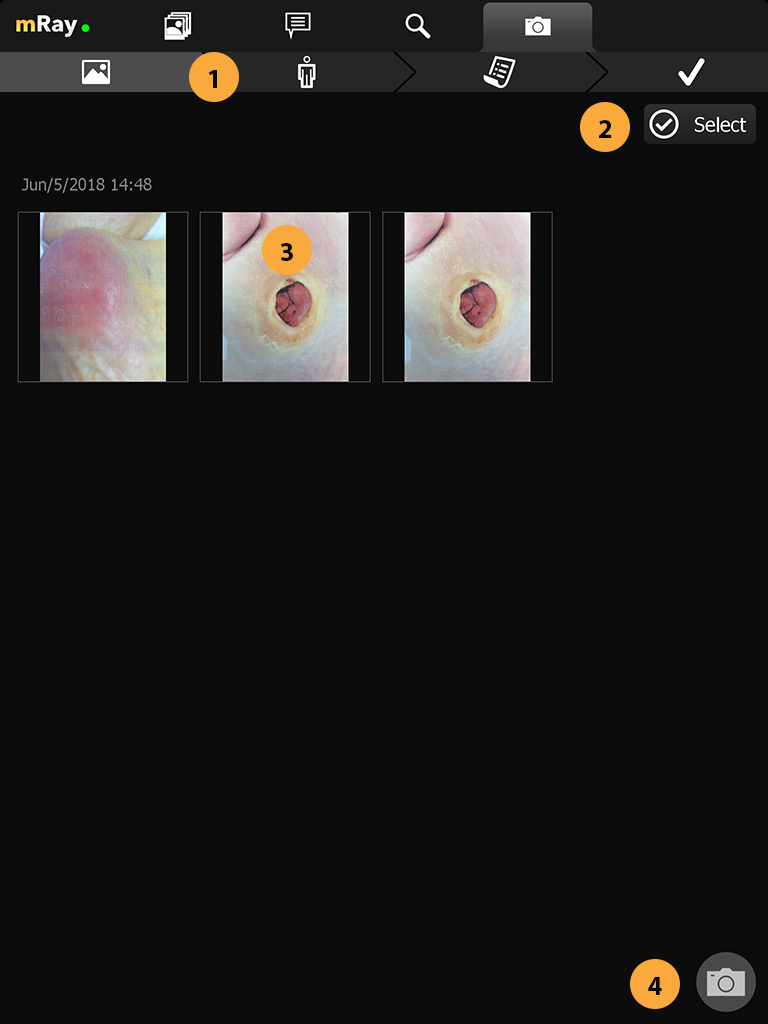

When the feature is enabled for the current user you’ll see an extra tab for the photo documentation and a button in your inbox to open the camera. By pressing on the camera button (Point 2) you’ll open the camera and be able to capture all the photos you require. A photo documentation workflow will be like the following

When you’ve captured all the photos you need press the photo stack (Point 3) to continue to the review process.

15.2. Photo gallery / Review

The review gallery displays all the photos that you have taken so far ordered by their capture date.

-

Navigation bar shows current progress and allows you to go to a step by tapping on it. By doing that you can only go to a previous step

-

Select button to enter image selection mode.

-

Click on a thumbnail in order to view a image.

-

Click on a thumbnail to add the image to the selection.

-

Button to select a row of images.

-

Cancel selection mode.

-

Deletes the selected images. Deleted images can not be restored.

-

Confirm selection and go to the next step.